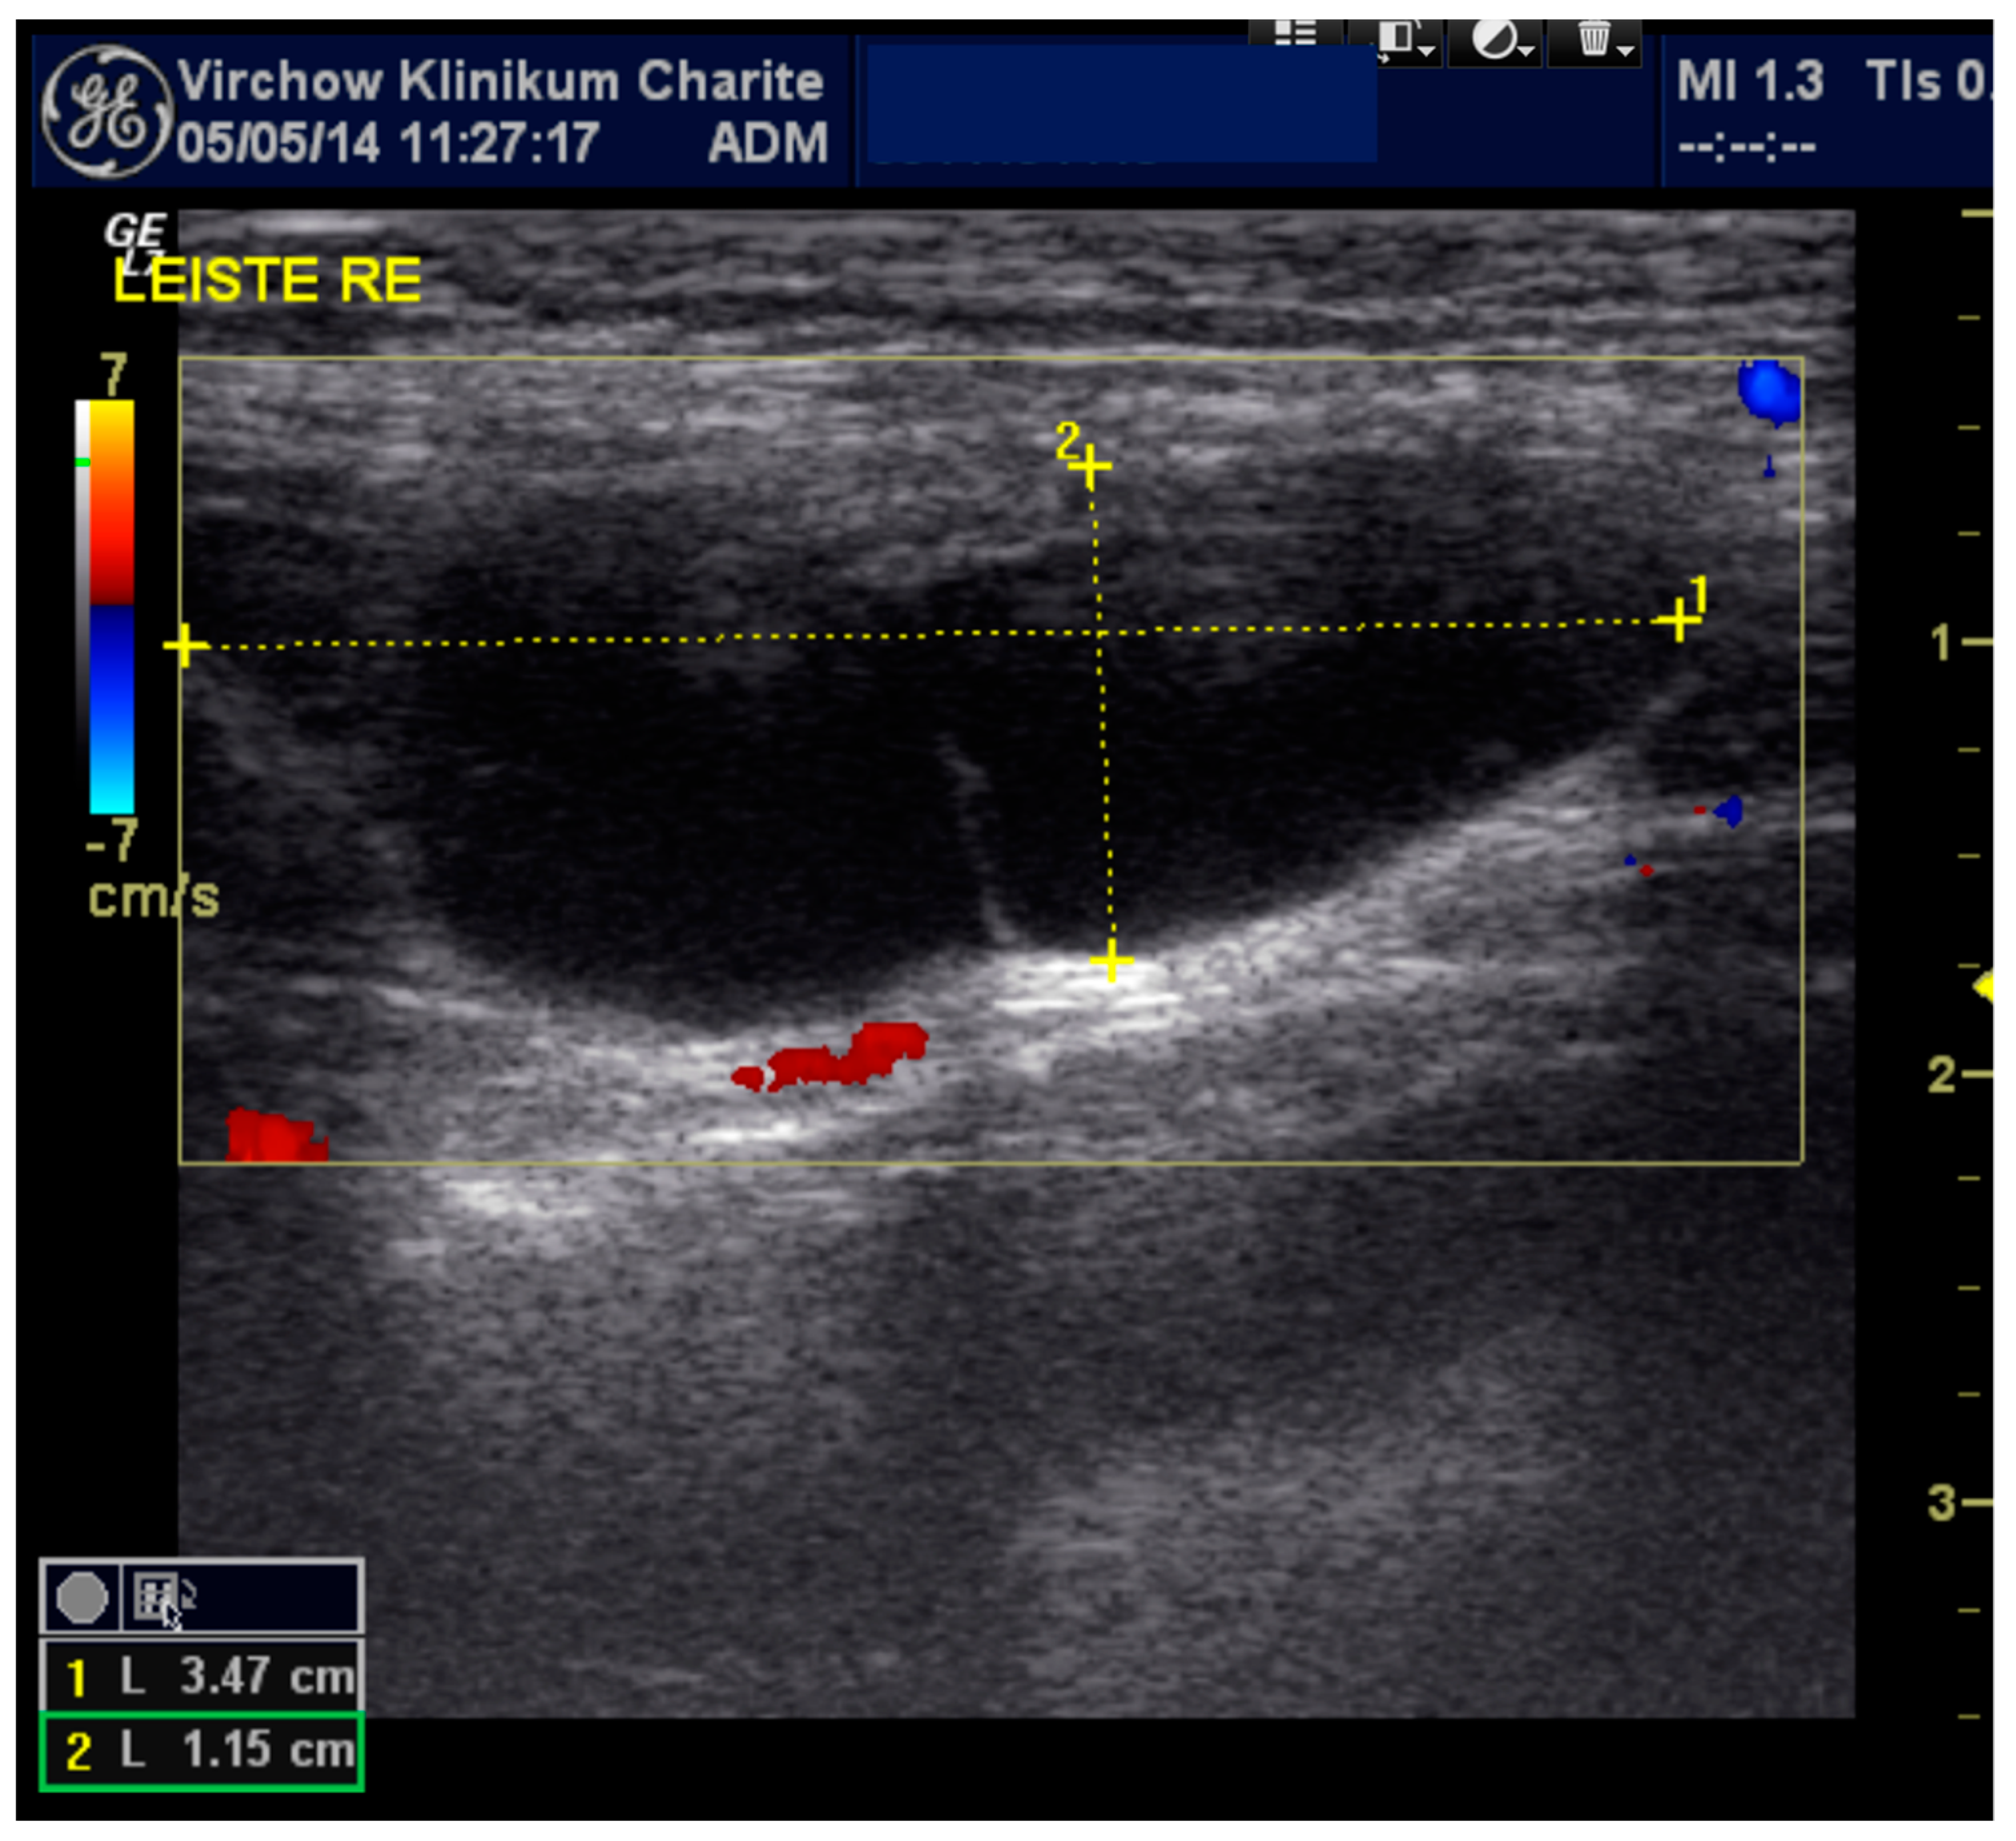

| Diagnostic Study | Ultrasound | Ultrasound | Ultrasound | Ultrasound and magnetic resonance imaging (MRI) | Ultrasound | MRI |